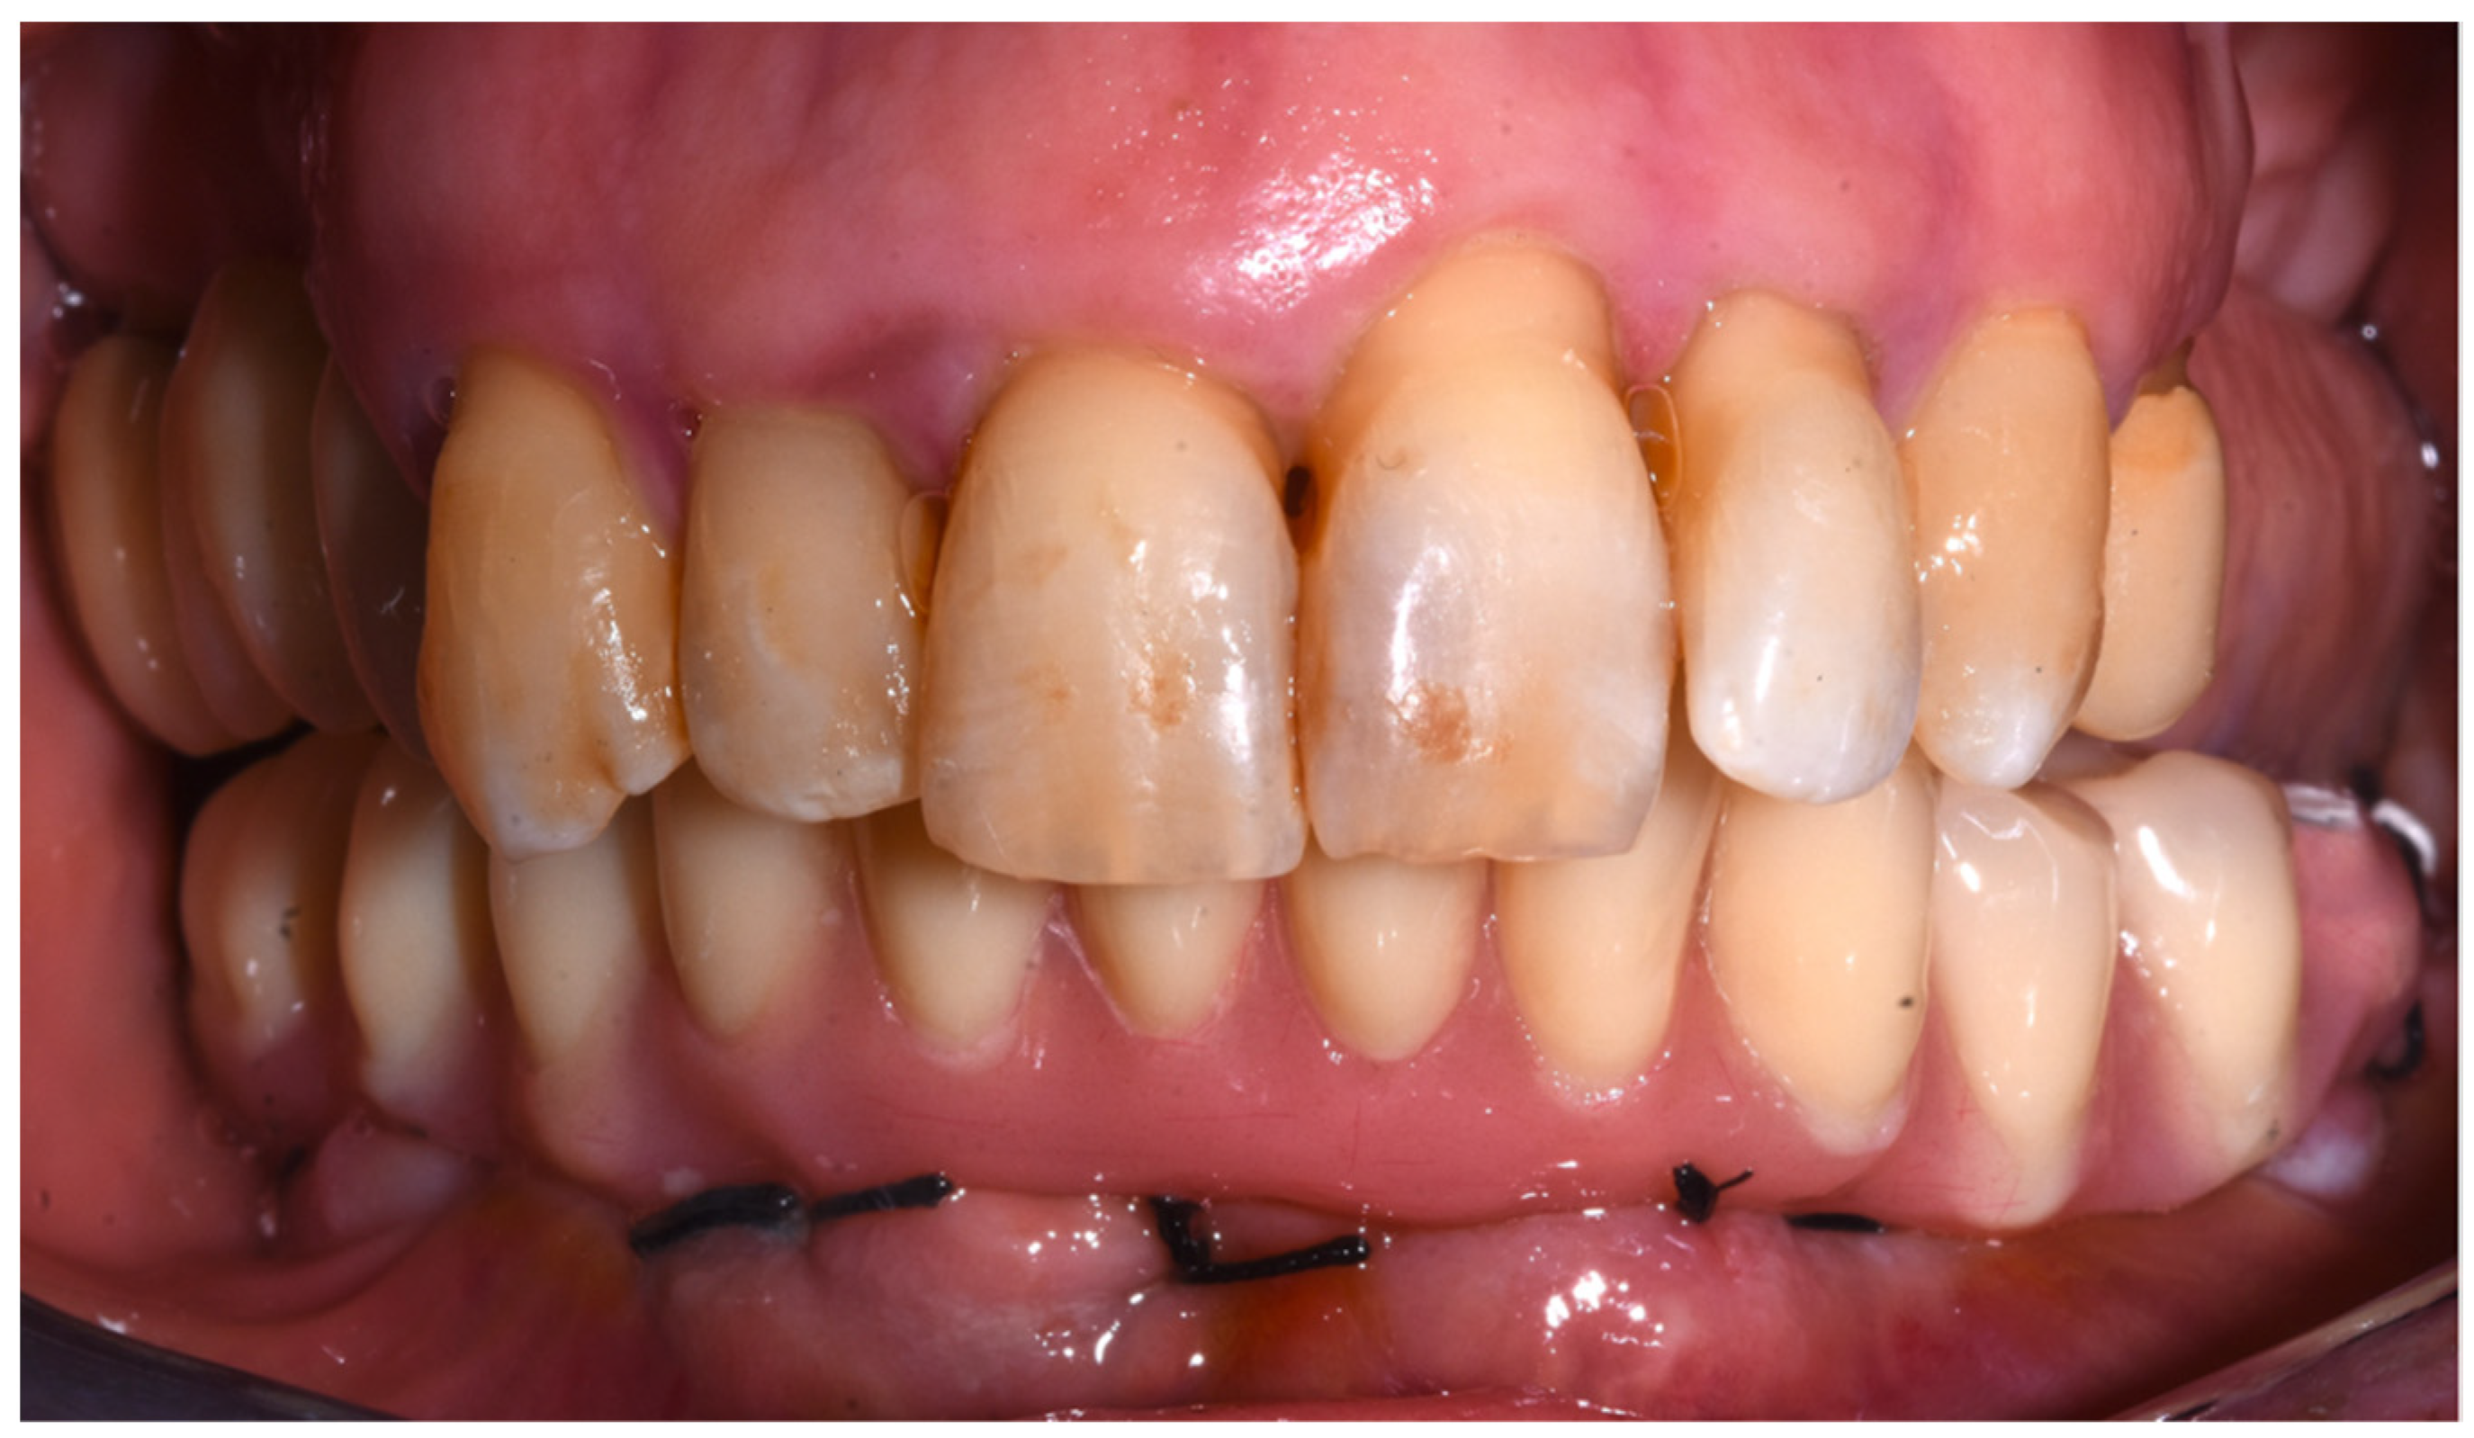

3. Results

- Probing depth (mm): Distal right (DR) implants showed 2 mm probing depth on the mesial side, 2 mm on the vestibular side, 3 mm on the distal side, and 3 mm on the lingual side. The anterior right (AR) implant showed 3 mm probing depth on the mesial side, 3 mm on the vestibular side, 2 mm on the distal side, and 3 mm on the lingual side. The anterior left (AL) implant showed 2 mm probing depth on the mesial side, 2 mm on the vestibular side, 3 mm on the distal side, and 3 mm on the lingual side. The distal left (DL) implant showed 2 mm probing depth on the mesial side, 2 mm on the vestibular side, 3 mm on the distal side, and 3 mm on the lingual side.

- Bleeding on probing (BOP): DR, AR, and DL implants presented one side each with BOP. No BOP was detected on the AL implant.

- No plaque was detected at any sites.